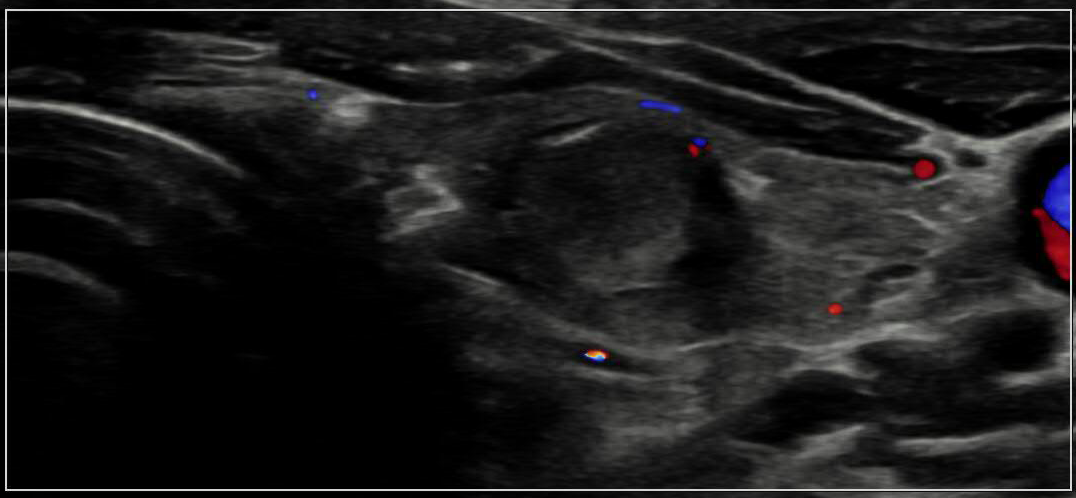

![]() |

Thyroid US 갑상선 초음파 고해상도 초음파를 이용해 갑상선의 크기, 형태, 결절 유무 및 내부 구조를 관찰하여 갑상선 결절, 낭종, 염증, 종양 등 이상 소견을 평가하는 검사입니다. |